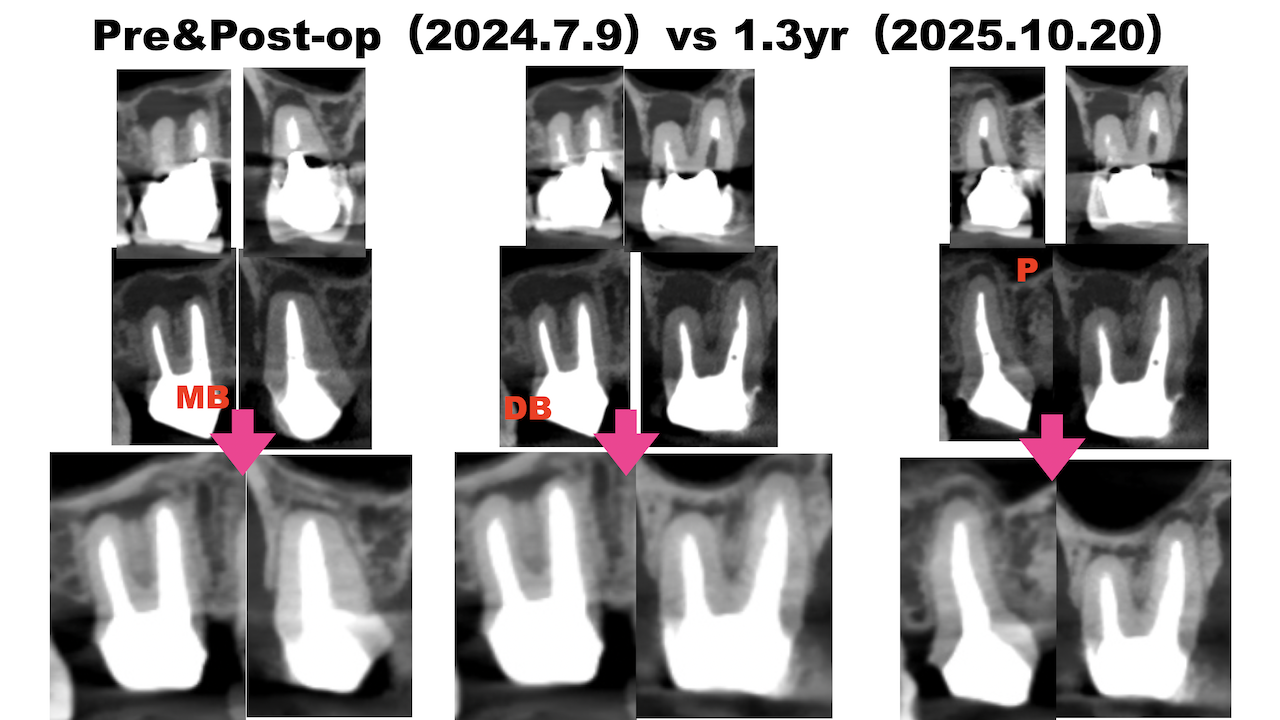

初診時+治療直後と比較した。

#3

#14

#16

劇的に病気が治癒している。

特に#16は凄まじい。

超音波洗浄しかできなかったのに根尖病変が治癒しているのだ。

免疫力が非常に強い患者さんなのだろう。